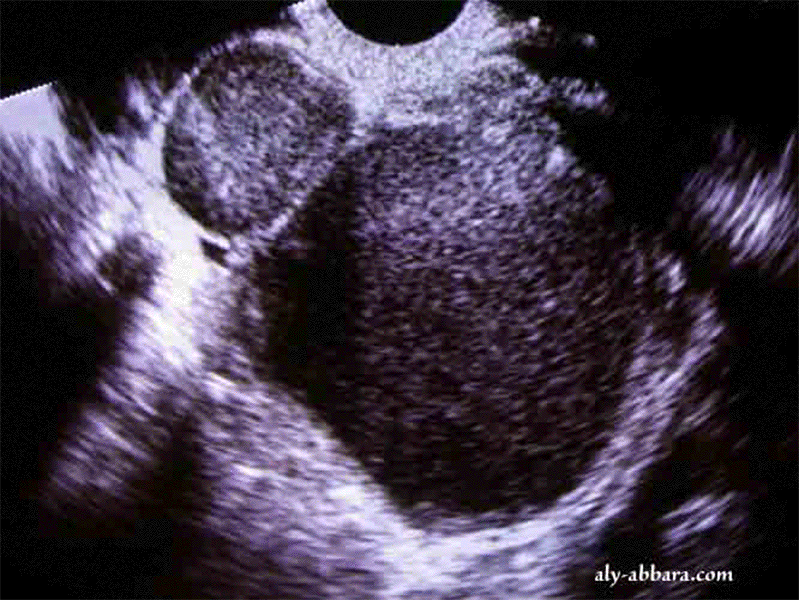

Edométriomes mutiples touchant les deux ovaires

Endométriomes ovariens multiples et bilatéraux

• Image échographique et du scanner montrant la présence de cinq endométriomes ovariens (kystes endométriosiques ovariens) : deux volumineux de 60 et 28 mm à l'ovaire gauche et 3 petits à l'ovaire droit, de 25, 9 et 8 mm de grands axes.

• L'acte opératoire confirme qu'il s'agit de kystes contenant un liquide chocolaté, avec importants phénomènes adhérentiels pelviens et en particulier, l'adhésion des deux ovaires en surplombant le fond utérin et en s'adhérant sur la face antérieure du rectum et la face postérieure de l'utérus.

• L'examen anatomopathologique de ces cinq kystes confirme qu'il s'agit de l'endométriose kystique ovarienne.